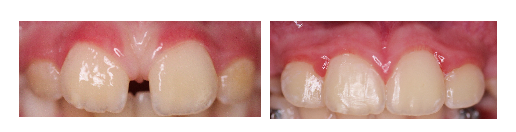

Lenk Orthodontics produces beautiful smiles. More importantly, the goal is to prevent problems before they happen…THIS IS A GREAT EXAMPLE…

EXCESS SPACING WAS NEGATIVELY IMPACTING THE DEVELOPMENT AND ERUPTION OF PERMANENT TEETH IN THE BONE…A LITTLE BIT OF EARLY CARE PREVENTED DAMAGE TO ROOTS, ECTOPIC ERUPTION, AND IMPACTION OF TEETH (IN SHORT, ALOT OF TIMELY AND EXPENSIVE TREATMENT AT THE AGE OF 13!!!)